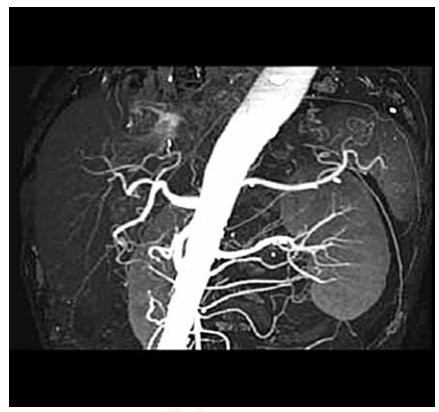

A imagem é o registro de uma angiografia tomográfica